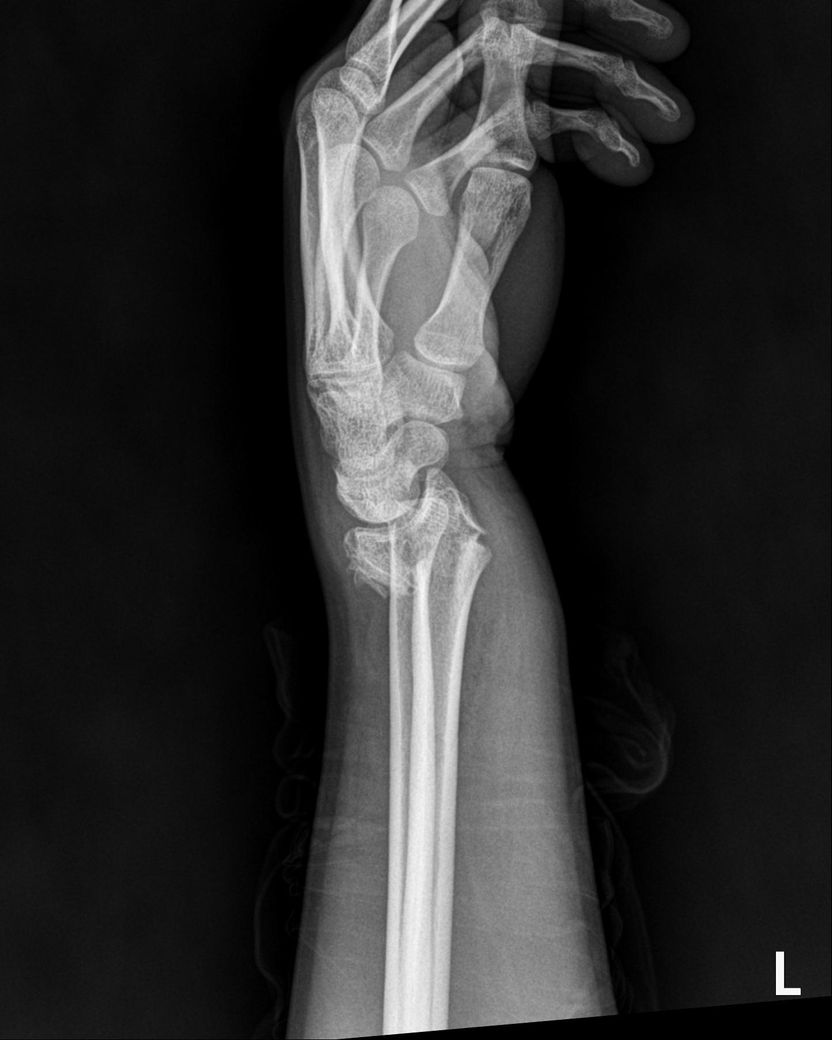

25년 12월에 빙판길에서 넘어져 요골 및 척골 모두 하단의 골절, 폐쇄성 이라는 진단을 받았으며

CT및 엑스레이는 12월 골절 당시 입니다

현재 상황을 종합적으로 보면, 폐쇄성 골절 후 금속 플레이트가 삽입된 상태에서 4월 이후 TFCC 부위 통증이 급격히 악화된 것은 단순한 염증 반응만으로 설명하기 어렵습니다. 골절 후 요척골 관계(distal radioulnar joint, DRUJ)의 정렬 변화, 플레이트 자체에 의한 기계적 자극, 또는 기존 봉합 부위의 재파열 가능성 모두를 고려해야 합니다. 플레이트가 있어 MRI를 아직 시행하지 못하셨다고 하셨는데, 이 부분이 현재 진단 판단의 가장 큰 제한점입니다.